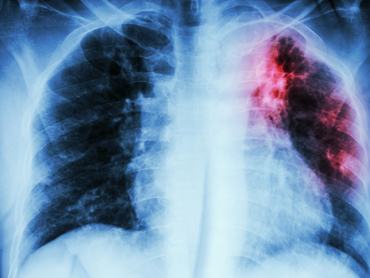

Ügyeskedve adhatják be a harmadik oltást

Rusvai Miklós virológus szerint a beoltottak 15-20 százalékánál nem alakul ki megfelelő védettség, és előfordul, hogy az orvosok harmadik oltást is beadnak, vagy az emberek Romániába mennek át egy újabb dózisért. A harmadik oltás beadását vagy a vakcinák keverését a hazai eljárásrend nem teszi lehetővé - írja a Telex.